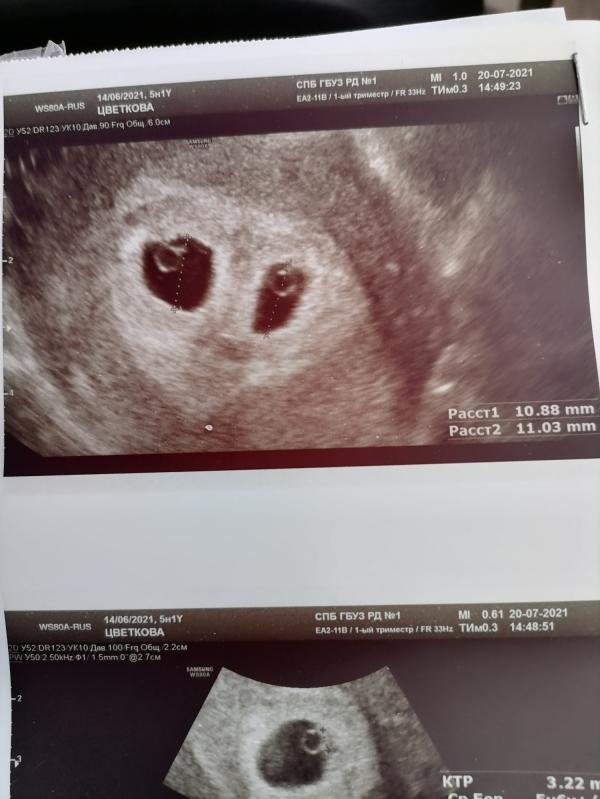

А потом я сказала репродуктологу: сажайте 2 эмбриона, последних, и я на этом завязываю попытки, надо жить дальше. И вот 2 полоски, странно высокий ХГЧ и вопрос врача: "А как я согласилась сразу двух подсадить?"))

Королевская двойня, не без сложностей, но довольно легкая беременность. Продажа и покупка новой квартиры, под расширяющуюся семью. И в декабре уже переезд на новое место!